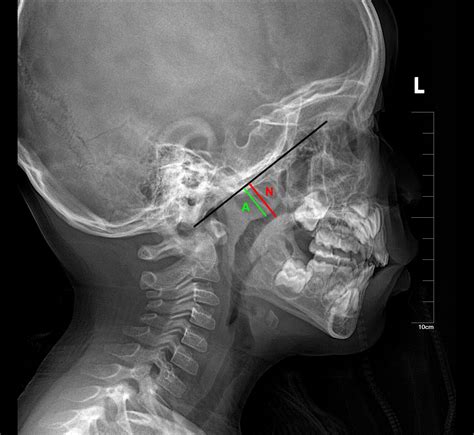

• Adenoids: These are located high up in the throat, behind the nose and the roof of the mouth (the soft palate). Because of this hidden location, they cannot be seen by looking directly into the mouth; a doctor requires a special mirror or a small, flexible camera to visualize them.

A specialist will likely perform a physical examination and may use an endoscope to view the nasal passage. In some cases, a sleep study might be ordered if there is concern regarding pediatric sleep apnea. By gaining a clear understanding of the location and severity of the enlargement, parents can work with their medical team to develop an effective, personalized treatment plan.